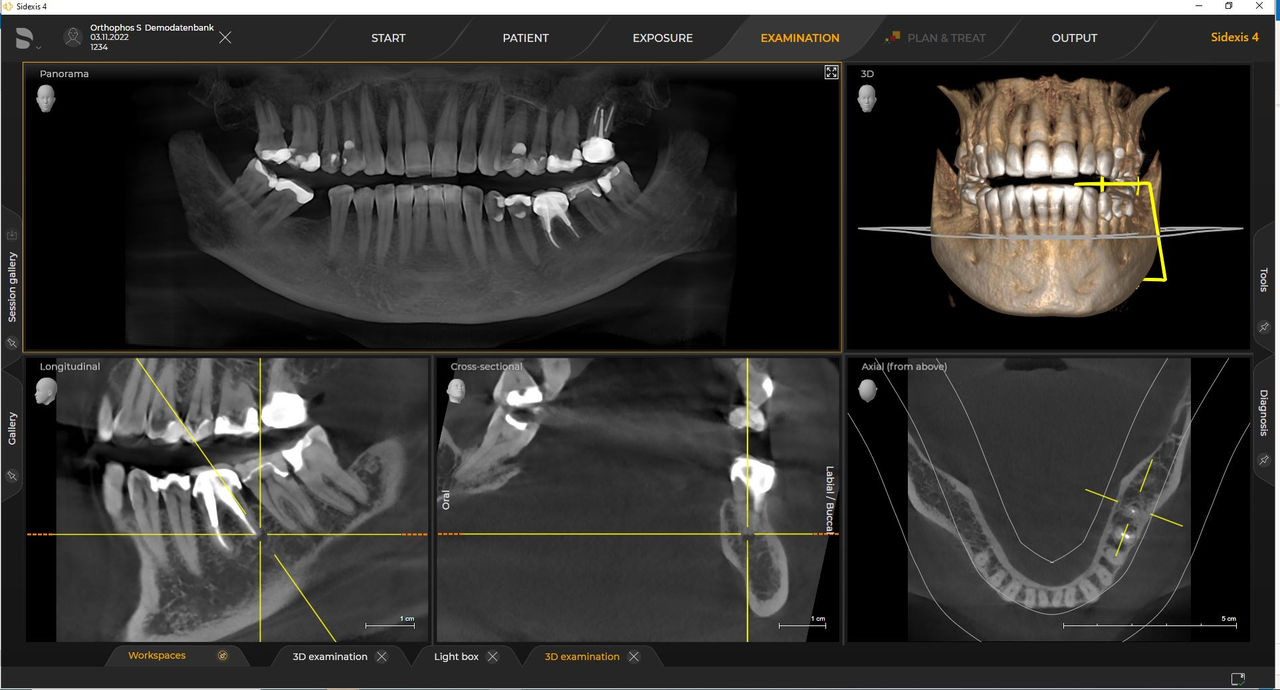

Con el modo de dosis baja inteligente 3D, obtiene imágenes 3D en el rango de dosis de una imagen radiológica 2D. En el modo HD (hasta 1400), las imágenes individuales se obtienen durante una única rotación y se convierten en un volumen 3D con hasta 80 μm para imágenes de bajo ruido en alta resolución.

Una amplia gama de tamaños de volumen para satisfacer sus diversas necesidades clínicas y de diagnóstico, desde Ø 5 x 5,5 cm hasta Ø 11 x 10 cm

Los requisitos siguen los del software de procesamiento de imágenes Sidexis 4 y Orthophos S. Para obtener más detalles, consulte los requisitos del sistema Sidexis 4 y los requisitos de instalación de Orthophos S.

Las unidades de radiología de Dentsply Sirona funcionan exclusivamente con Sidexis 4. Sin embargo, la migración de datos de Sidexis XG a Sidexis 4 es muy fácil. Sidexis 4 permite una experiencia digital completa con las últimas herramientas